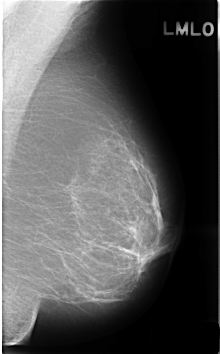

C_0370_1.LEFT_MLO

LEFT_MLO LINES 4592 PIXELS_PER_LINE 2848 BITS_PER_PIXEL 12 RESOLUTION 50 NON_OVERLAY